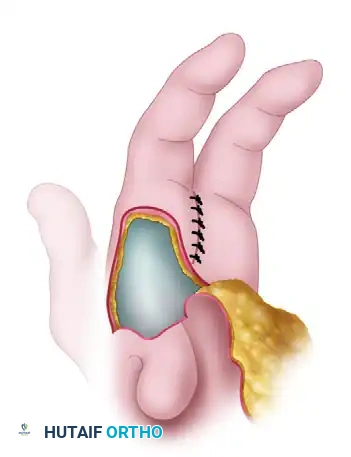

4. Wound Closure and Web Space Inset

- Suture the skin between the ring and index fingers, closing the central cleft.

- Inset the small, longitudinal flap into the ulnar side of the index finger to recreate a smooth, U-shaped commissure.

- Transpose the large palmar-based cleft flap into the newly opened space between the index finger and the abducted thumb.

Relationship of the thumb adduction contracture release and the palmar flap. If the palmar flap is insufficient to cover the defect, a full-thickness or split-thickness skin graft must be utilized.

- Tension-Free Closure: Never place these flaps under tension. Ischemia will lead to flap necrosis and severe secondary contracture. If the palmar flap does not completely cover the dorsal defect, harvest a split-thickness or full-thickness skin graft to achieve complete, tension-free coverage.

- Insert a small surgical drain if dead space or oozing is a concern.